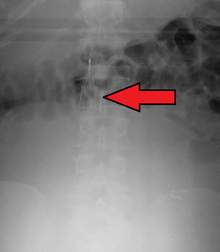

Placement

IVC filters are placed endovascularly, meaning that they are inserted via the blood vessels. Historically, IVC filters were placed surgically, but with modern filters that can be compressed into much thinner catheters, access to the venous system can be obtained via the femoral vein (the large vein in the groin), the internal jugular vein (the large vein in the neck) or the arm veins with one design. Choice of route depends mainly on the number and location of any blood clot within the venous system. To place the filter, a catheter is guided into the IVC using fluoroscopic guidance, then the filter is pushed through the catheter and deployed into the desired location, usually just below the junction of the IVC and the lowest renal vein.[39]

Review of prior cross-sectional imaging or a venogram of the IVC is performed before deploying the filter to assess for potential anatomic variations, thrombi within the IVC, or areas of stenoses, as well as to estimate the diameter of the IVC. Rarely, ultrasound-guided placement is preferred in the setting of contrast allergy, renal insufficiency, and when patient immobility is desired. The size of the IVC may affect which filter is deployed, as some (such as the Birds Nest) are approved to accommodate larger cavae. There are situations where the filter is placed above the renal veins (e.g. pregnant patients or women of childbearing age, renal or gonadal vein thromboses, etc.). Also, if there is duplication of the IVC, the filter is placed above the confluence of the two IVCs [40] or a filter can be placed within each IVC.[41]